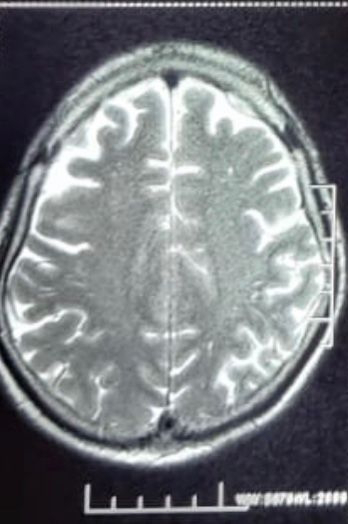

MRI Brain:

Revealed Cerebral and Cebellar atrophy

Chronic ischaemic changes were also noted

T2 weighted image:

On neuroimaging his mri brain reveled cerebral and cerebellar changes with chronic ishaemic changes.